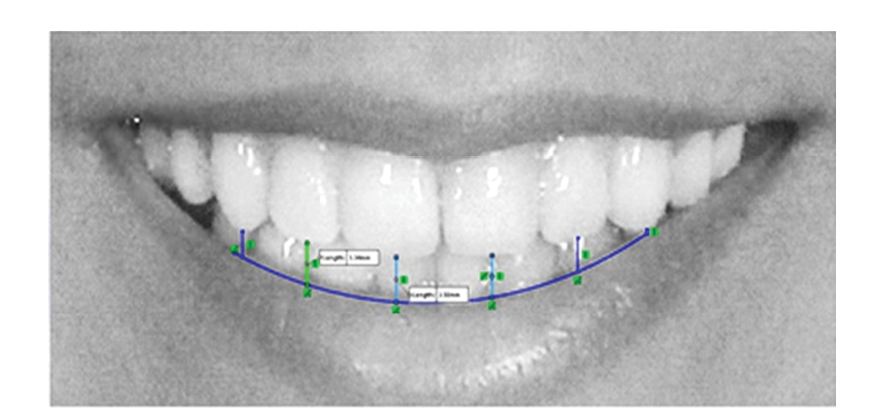

To assess the smile arc, a line was drawn tangent to the upper border of the lower lip, and the distance between the upper anterior teeth and this line was measured along a perpendicular line drawn from the midpoint of the incisal edge of the incisors and the tip of the canine cusps on both sides [23] (Figure-2). Additionally, the number of visible teeth during smiling on each side was counted.

Figure 2. Evaluation of smile arc relative to the upper border of lower lip